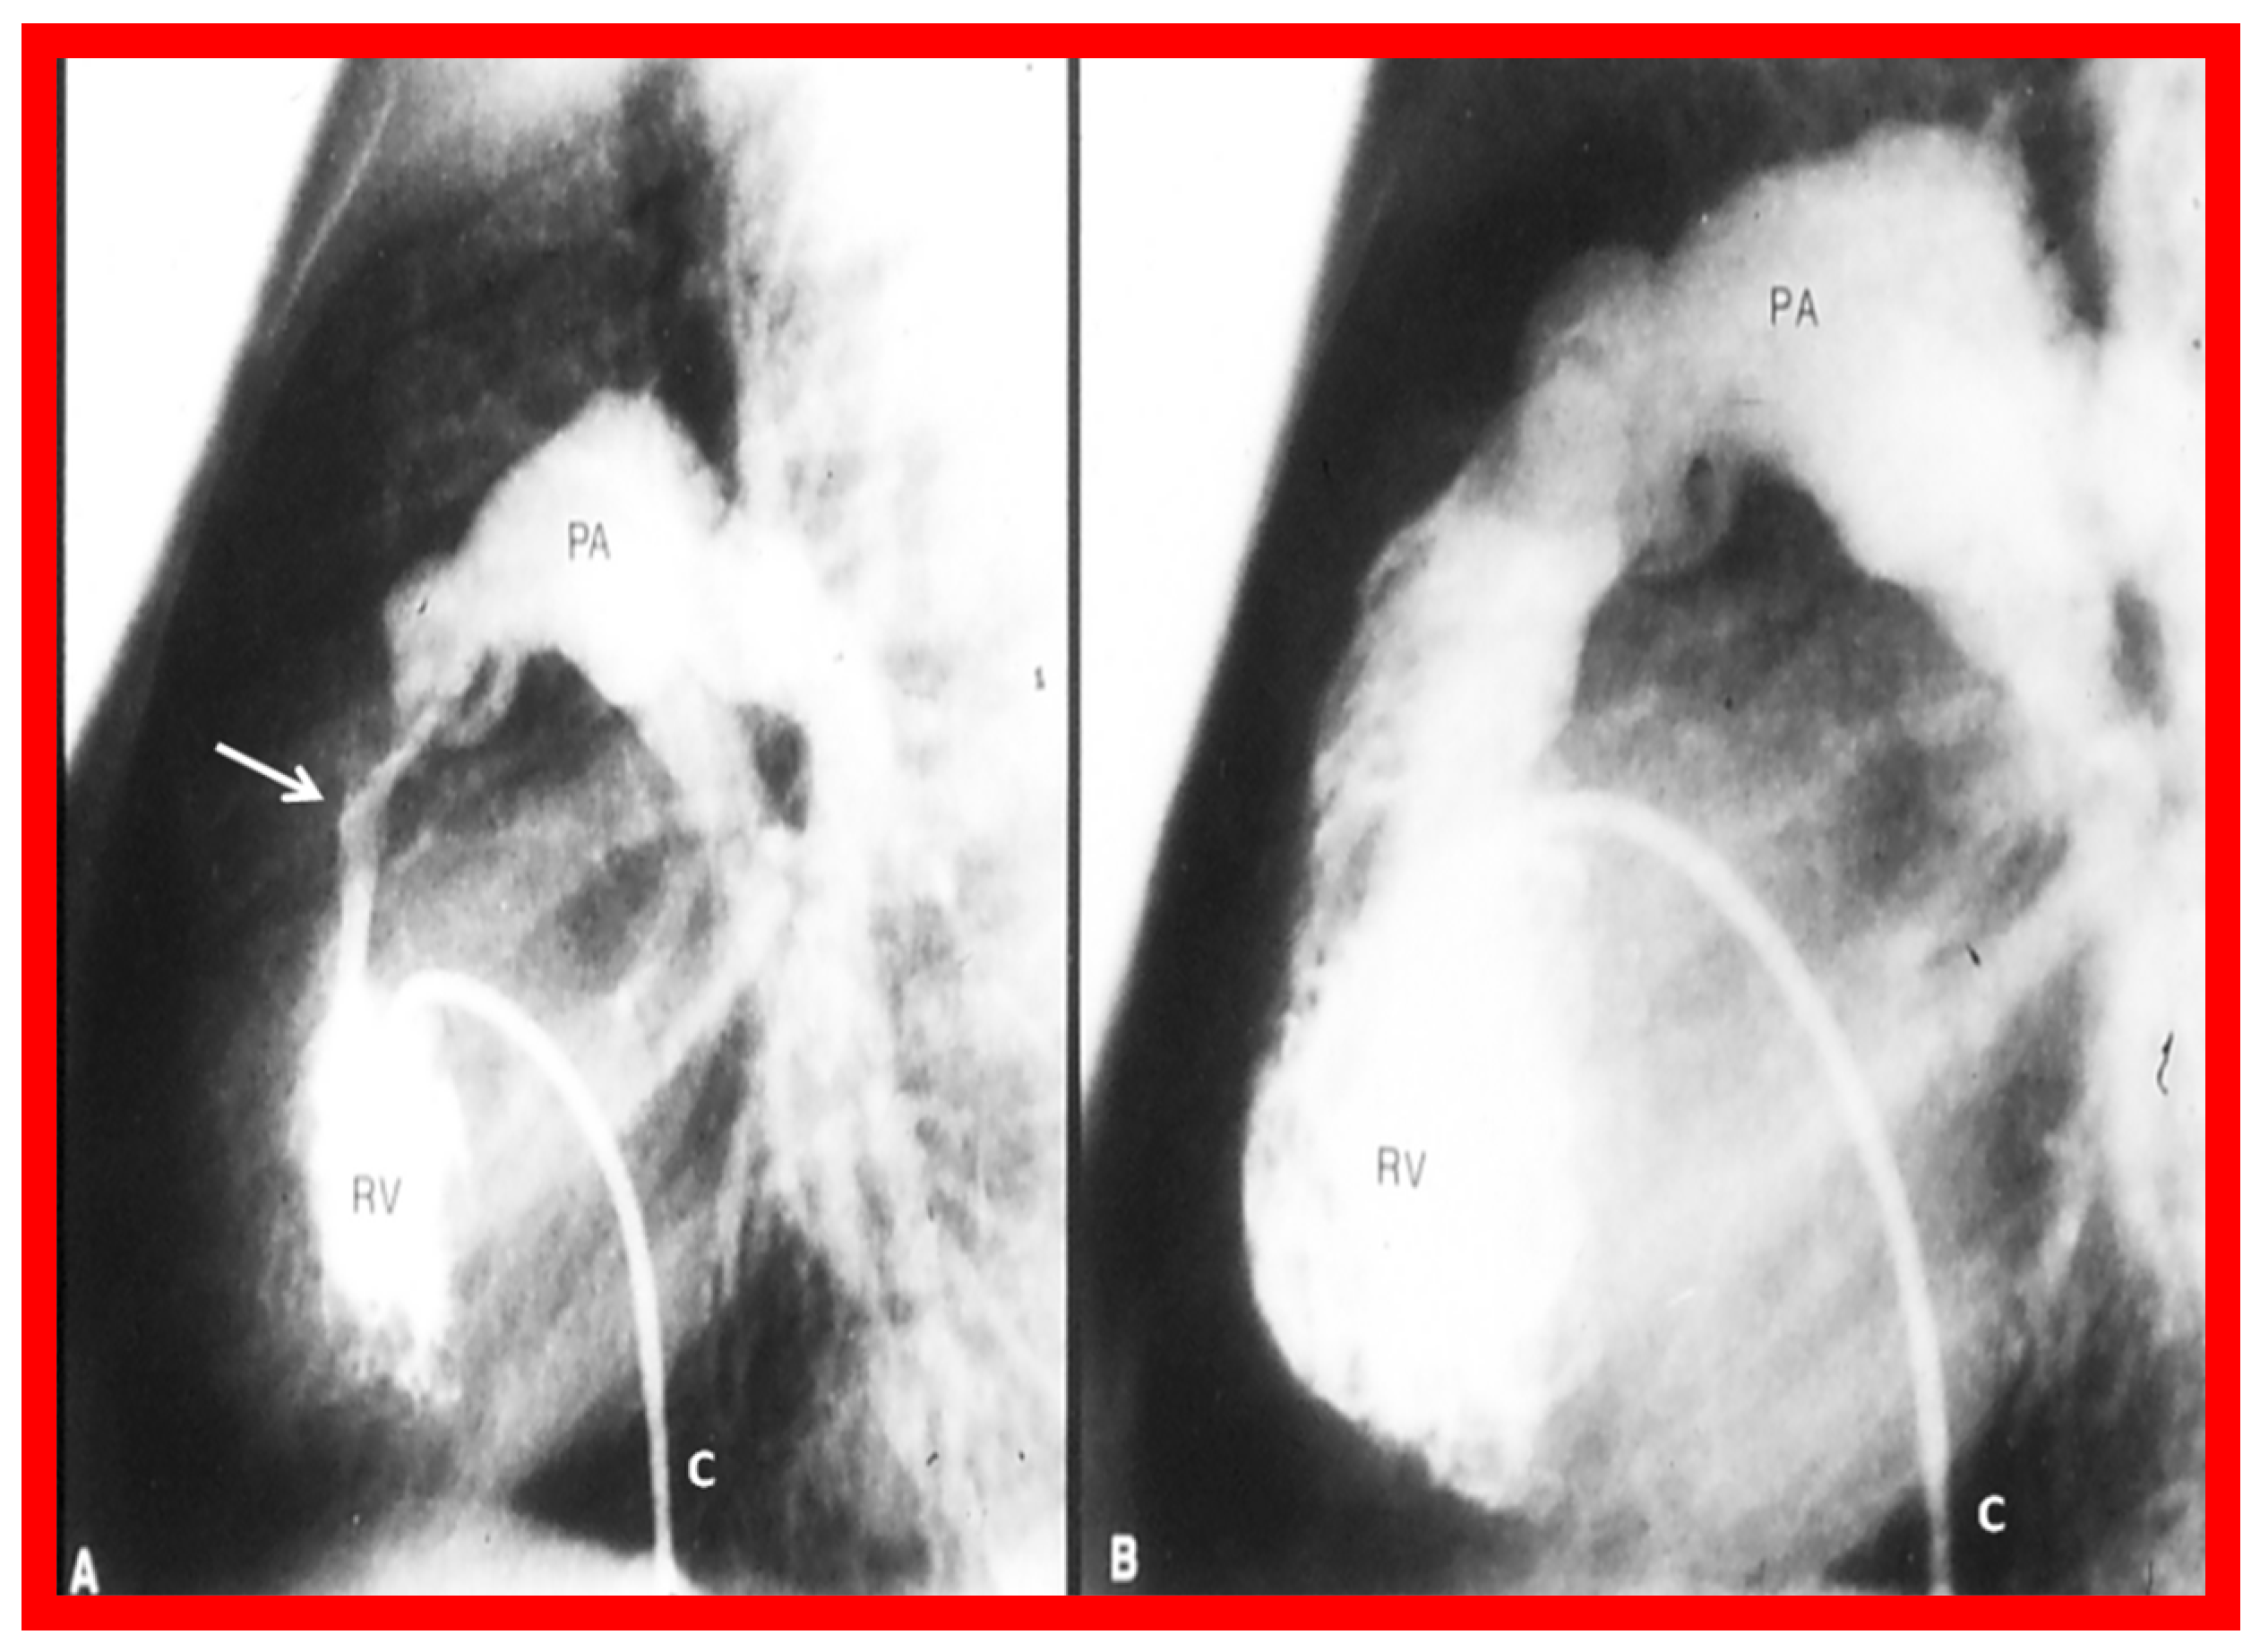

| 3. Perform RV cine-angiography and scrutinize these angiograms for infundibular obstruction both before and 15 min after valvuloplasty *. |

| 8. If angiographic (Figure 2A), pressure (Figure 1) and/or echo-Doppler (Figure 3B) data suggest, significant residual infundibular obstruction, beta blocker drug therapy may be necessary; we recommend it if the residual gradient is more than 50 mmHg [2,6]. |